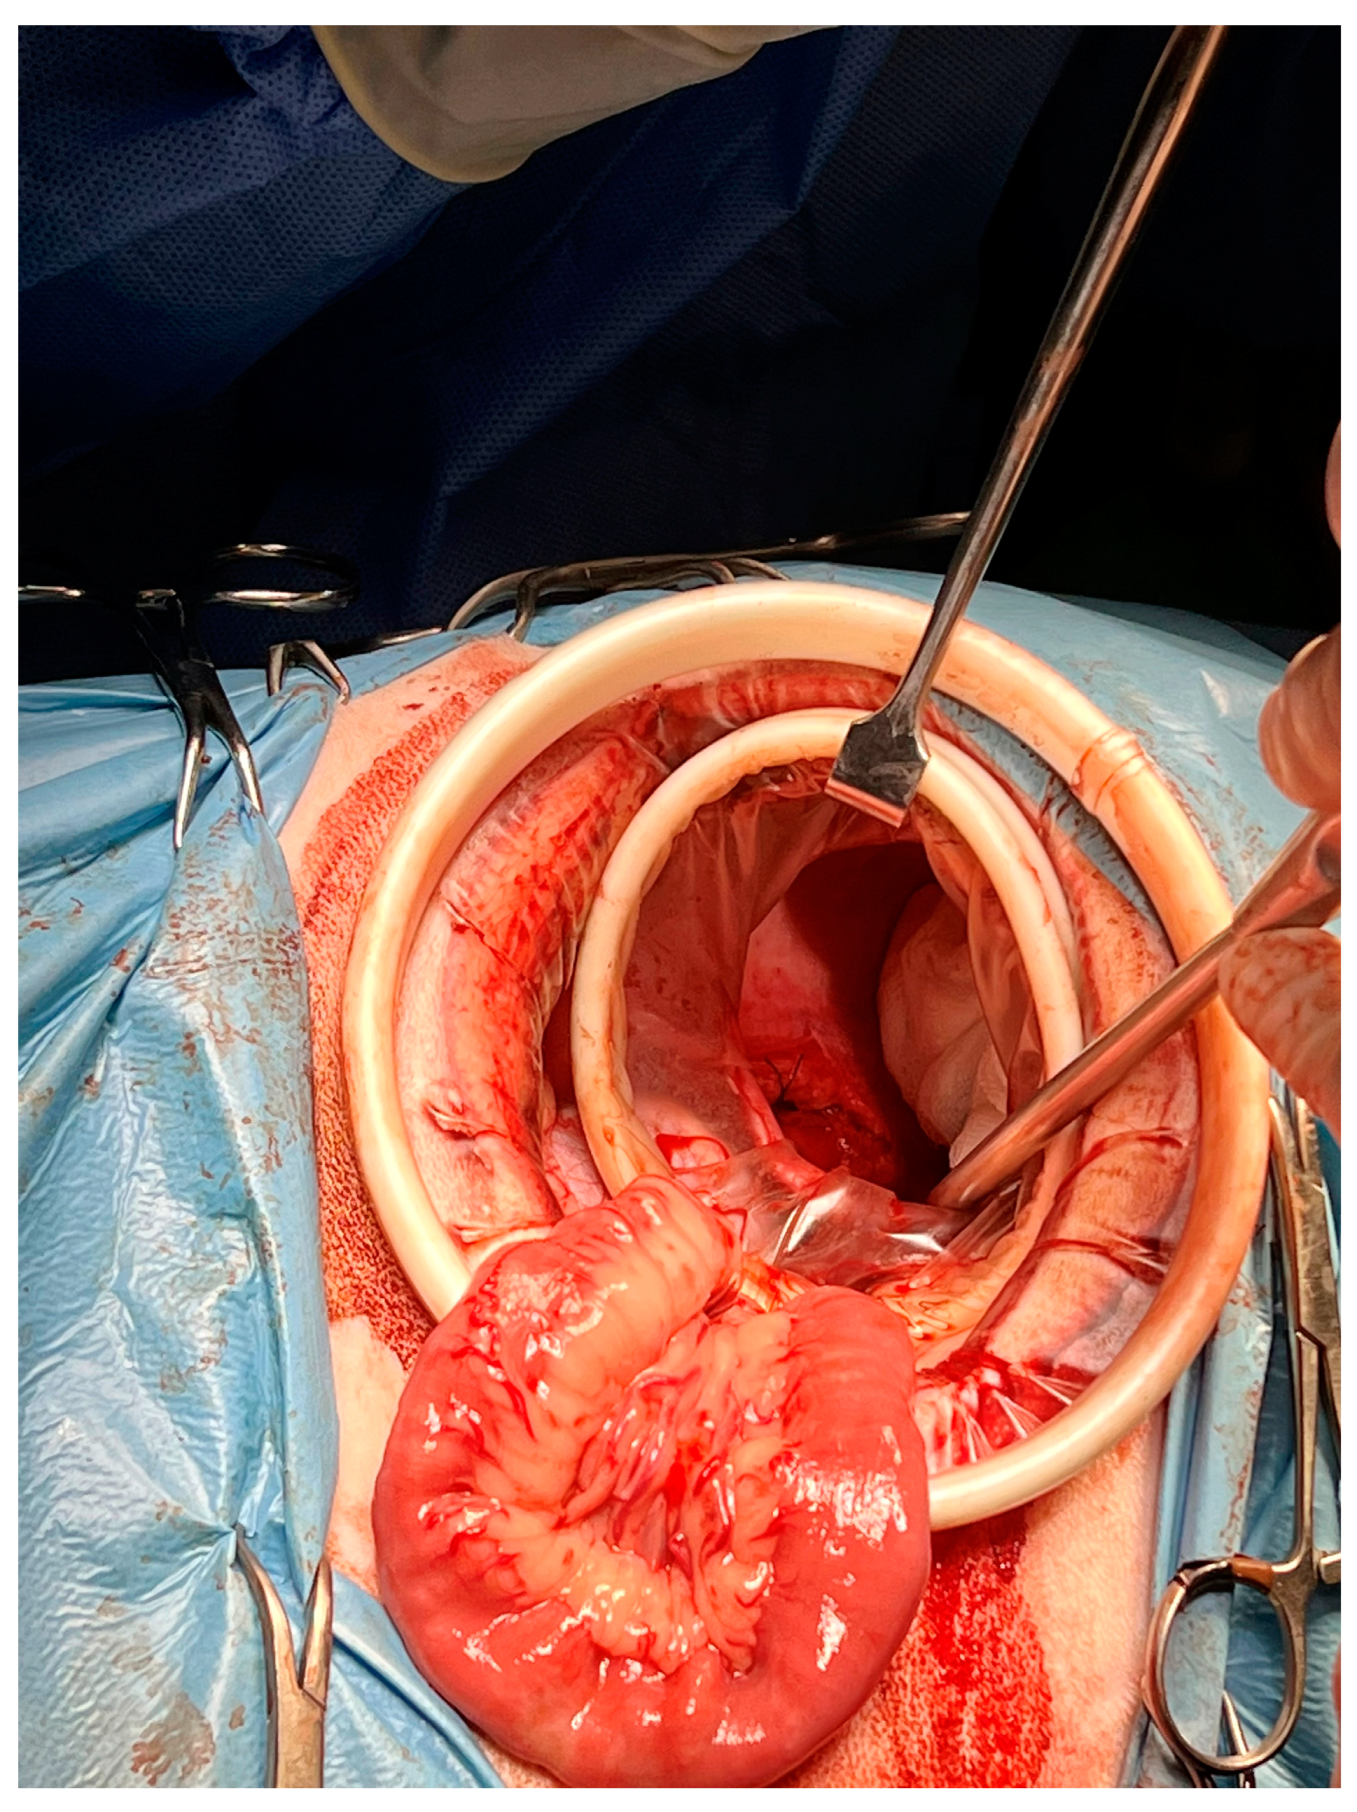

2. Materials and Methods

2.2. Surgery